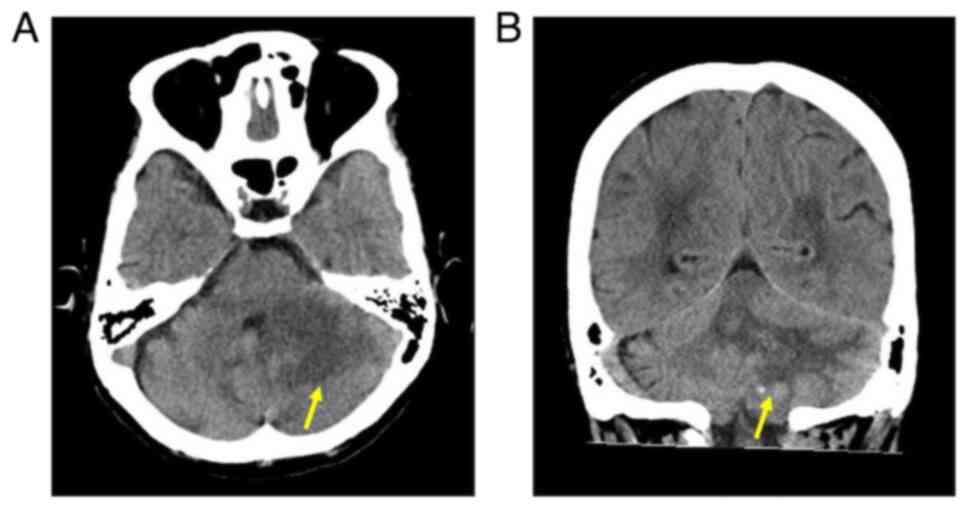

Methotrexate‑related other iatrogenic immunodeficiency‑associated lymphoproliferative disorder (MTX‑OIIA‑LPD) is prone to extranodal involvement but rarely involves the central nervous system (CNS). The present study reports a case of MTX‑OIIA‑LPD of the CNS discovered during medication‑related osteonecrosis of the jaw (MRONJ) treatment in a 76‑year‑old woman with rheumatoid arthritis (RA). The chief complaint of the patient was bone exposure and pain in the right mandibular molar. The patient had been receiving MTX for RA and alendronate sodium hydrate for osteoporosis, followed by denosumab. Treatment was initiated based on a diagnosis of MRONJ. However, the patient experienced lightheadedness and floating dizziness afterwards. Examinations revealed scattered neoplastic lesions in the brain. The histopathological diagnosis was diffuse large B‑cell lymphoma. A systemic search also revealed adrenal involvement. Since the patient was taking MTX, a diagnosis of MTX‑OIIA‑LPD was made and MTX was discontinued. Chemotherapeutic agents were administered since the central lesions became symptomatic. The MTX‑OIIA‑LPD lesions in the brain and adrenal glands completely resolved 8 months after onset. The physical condition of the patient improved, and the bone‑exposed areas became epithelialized. Reports on MTX‑LPD in the oral and maxillofacial region are few, which may delay its diagnosis. Therefore, biopsy of oral lesions in patients with MRONJ who are taking MTX and collaboration with related diagnostic departments, such as rheumatology and hematology, must be done to initiate the diagnosis and treatment of extraoral MTX‑LPD.